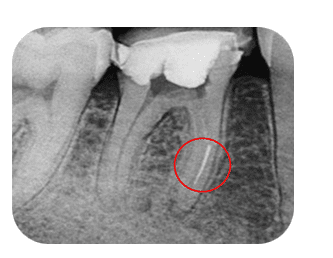

| Canal Anatomy | Straight canal | Sharp curvature | Curved canals increase risk of perforation and transportation. |

- Cyclic fatigue — repeated flexing in curved canals leading to fracture.

- Curved canals